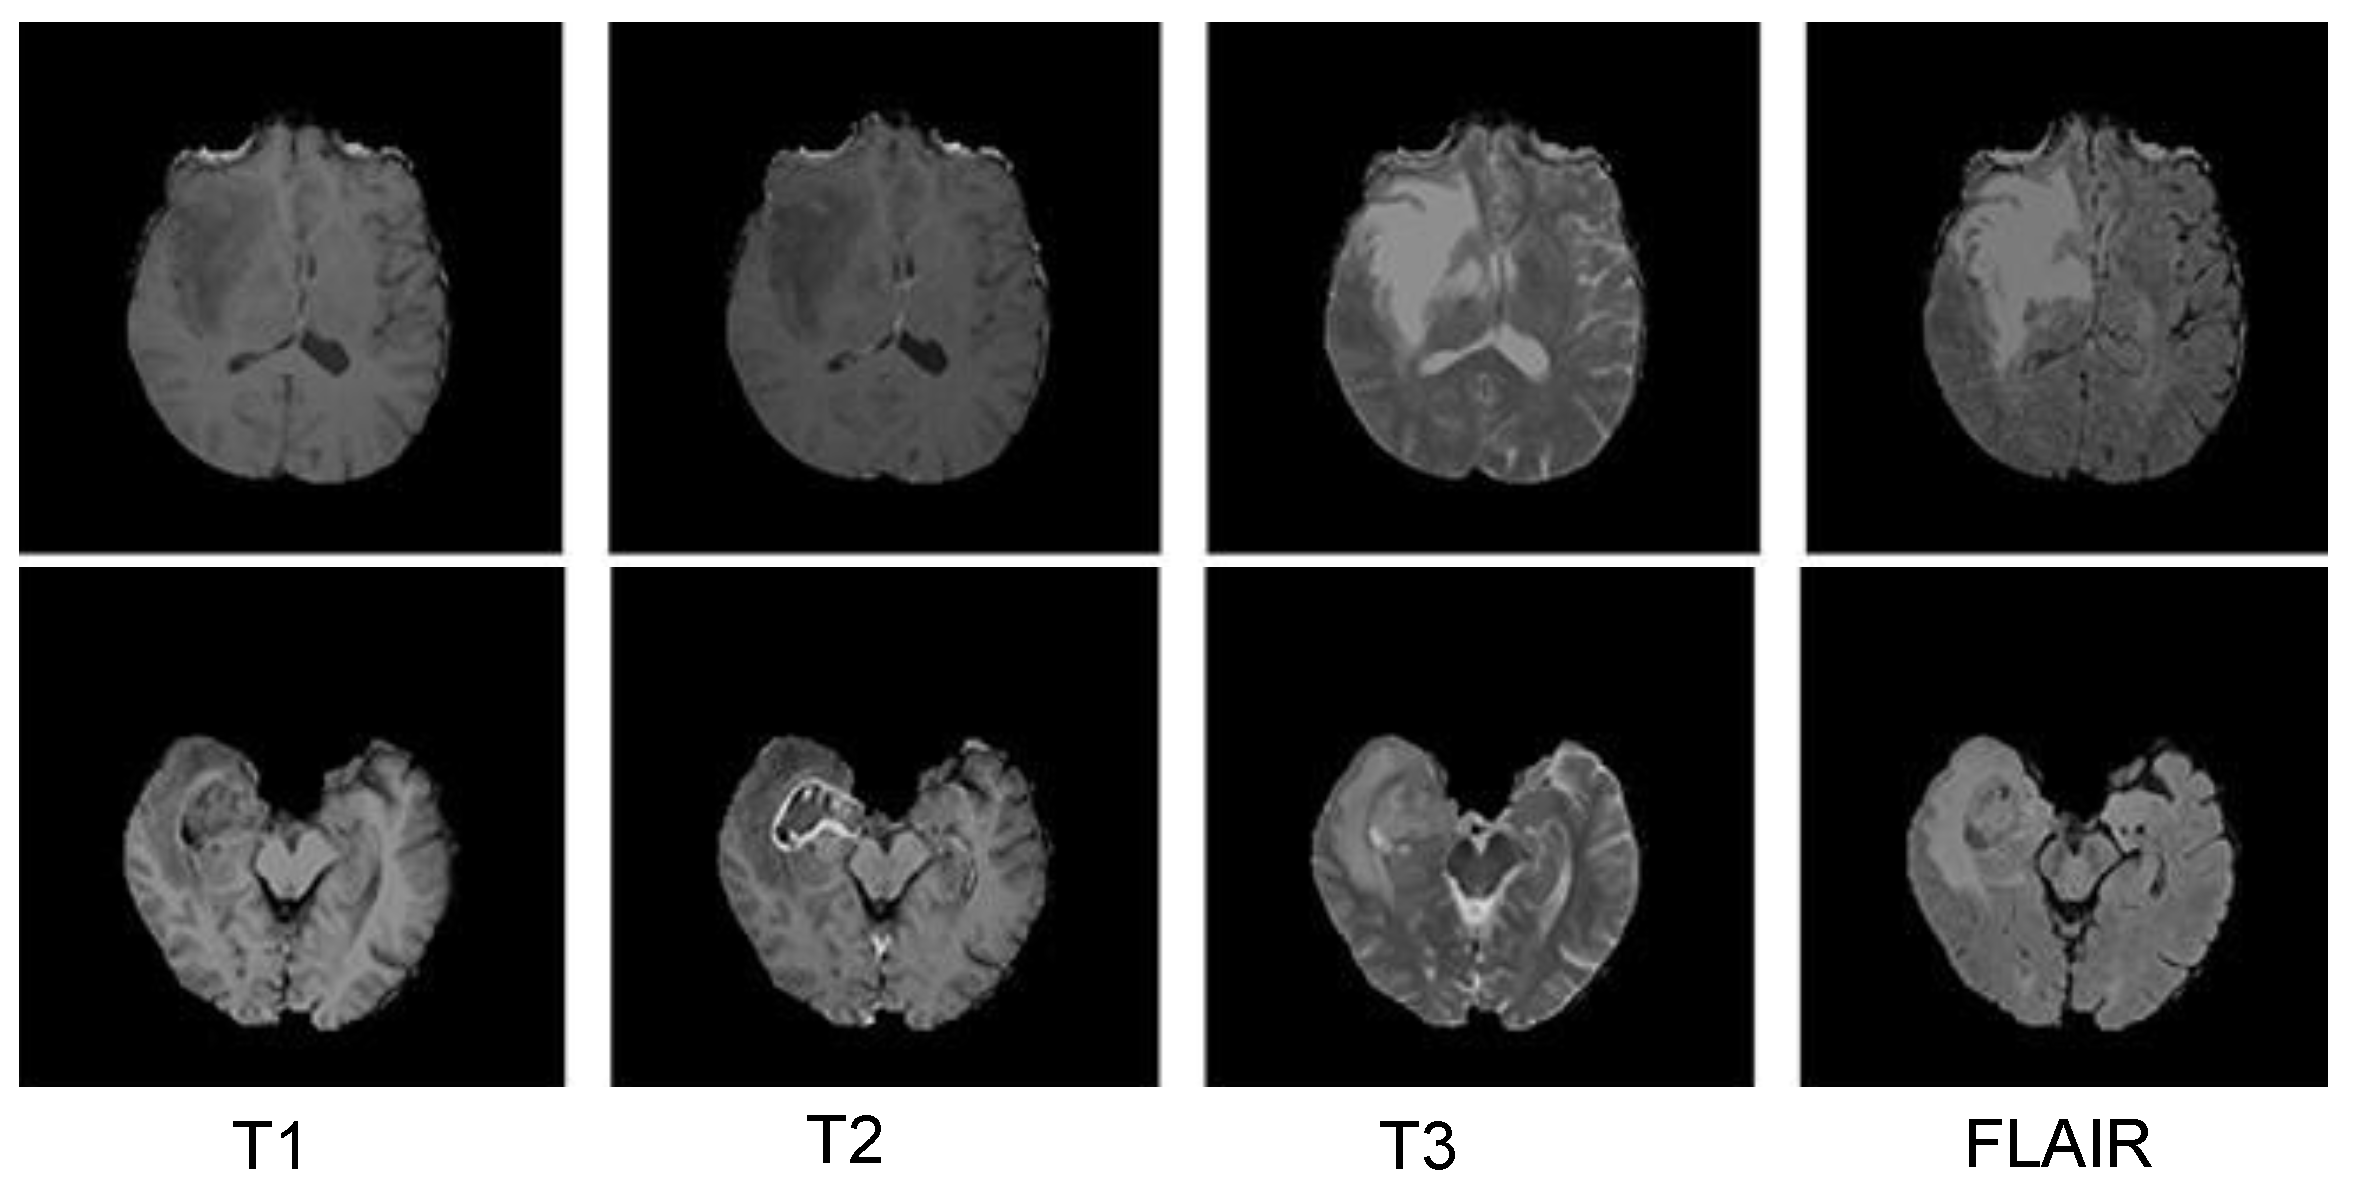

3.5.1. BraTS 2018 Dataset

3.5.2. Figshare Dataset